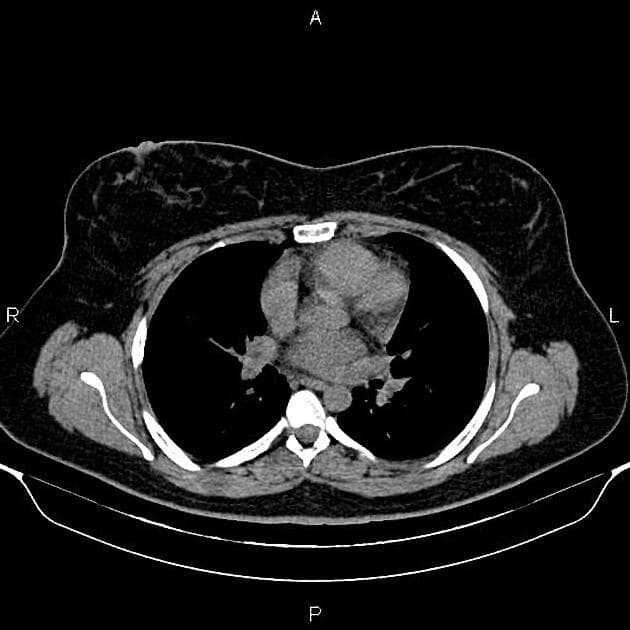

Hai tổn thương gan được phát hiện tình cờ trên cắt lớp vi tính thực hiện để tìm nguyên nhân đổ mồ hôi về đêm.

Hai tổn thương bắt thuốc ở phân đoạn 6 và 3, vùng trung tâm giảm tỷ trọng (không bắt thuốc) và không có hiện tượng thải thuốc (washout).

Hình ảnh điển hình của tăng sản khu trú dạng nốt (focal nodular hyperplasia), là một trong số ít các tổn thương có khả năng tích tụ mạnh thuốc cản quang đặc hiệu tế bào gan.